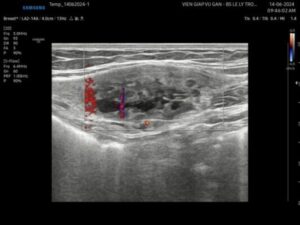

Ca Lâm Sàng 179: Bướu Sợi Tuyến Phức Tạp

Bs. Lê Lý Trọng Hưng Bs. Nguyễn Thị Thu Anh Bệnh nhân nữ 27 tuổi,...